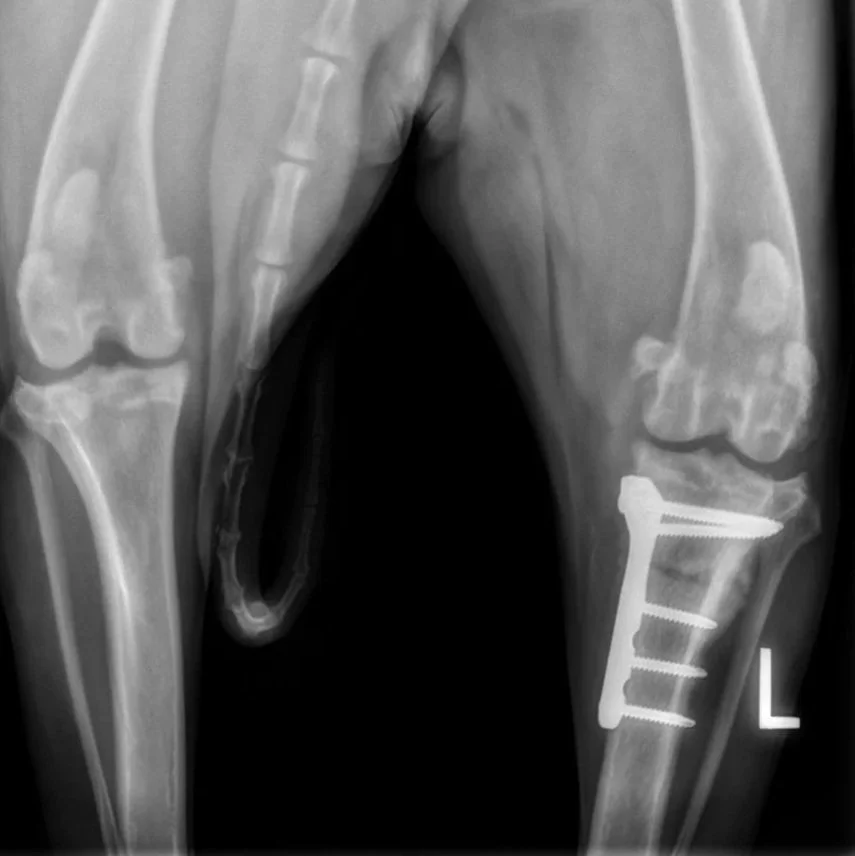

The plate and screws required to stabilize the bone after a tibial plateau leveling osteotomy (TPLO) are easily visible in a radiograph.

~$5000 per knee

TPLO Surgery: Mechanical Stabilization

The Tibial Plateau Leveling Osteotomy (TPLO) is widely considered the gold standard for large, active, or young dogs with complete CCL ruptures. The surgery involves a precise radial cut in the tibia to rotate the slope of the bone, effectively neutralizing the force that causes the femur to slide backward. Once the bone is stabilized with a specialized plate and screws, the ligament is no longer needed for the dog to walk normally.

TPLO has a high success rate, with most dogs returning to full athletic function within 4-5 months. At Two Rivers, we emphasize that surgery is only the first half of the journey; the second half is a 10-week post-op rehab period. We strongly recommend a professional rehab package starting the week of surgery to ensure the bone heals correctly and the muscles regain their full strength. This includes photobiomodulation therapy, injectable joint care with Adequan, weekly sessions in the underwater treadmill, and both an in-clinic and at-home exercise regimen. This helps ensure that your dog will be ready for off-leash activity after those 10 weeks without a decline in muscle and bone health.